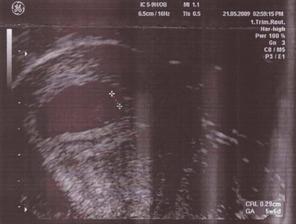

21.5.09: utz, kontrola u MUDr. Skřivánka, 5tt+6, ASP viděna, srdeční tep kmital jako blázen 🙂 velikost 2,9mm...